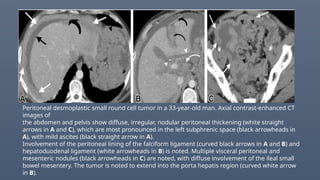

Peritoneal desmoplastic small round cell tumor in a 33-year-old man. Axial contrast-enhanced CT

images of

the abdomen and pelvis show diffuse, irregular, nodular peritoneal thickening (white straight

arrows in A and C), which are most pronounced in the left subphrenic space (black arrowheads in

A), with mild ascites (black straight arrow in A).

Involvement of the peritoneal lining of the falciform ligament (curved black arrows in A and B) and

hepatoduodenal ligament (white arrowheads in B) is noted. Multiple visceral peritoneal and

mesenteric nodules (black arrowheads in C) are noted, with diffuse involvement of the ileal small

bowel mesentery. The tumor is noted to extend into the porta hepatis region (curved white arrow

in B).

Peritoneal desmoplastic smallround cell tumor in a 33-year-old man. Axial contrast-enhanced CT images of the abdomen and pelvis show diffuse, irregular, nodular peritoneal thickening (white straight arrows in A and C), which are most pronounced in the left subphrenic space (black arrowheads in A), with mild ascites (black straight arrow in A). Involvement of the peritoneal lining of the falciform ligament (curved black arrows in A and B) and hepatoduodenal ligament (white arrowheads in B) is noted. Multiple visceral peritoneal and mesenteric nodules (black arrowheads in C) are noted, with diffuse involvement of the ileal small bowel mesentery. The tumor is noted to extend into the porta hepatis region (curved white arrow in B).